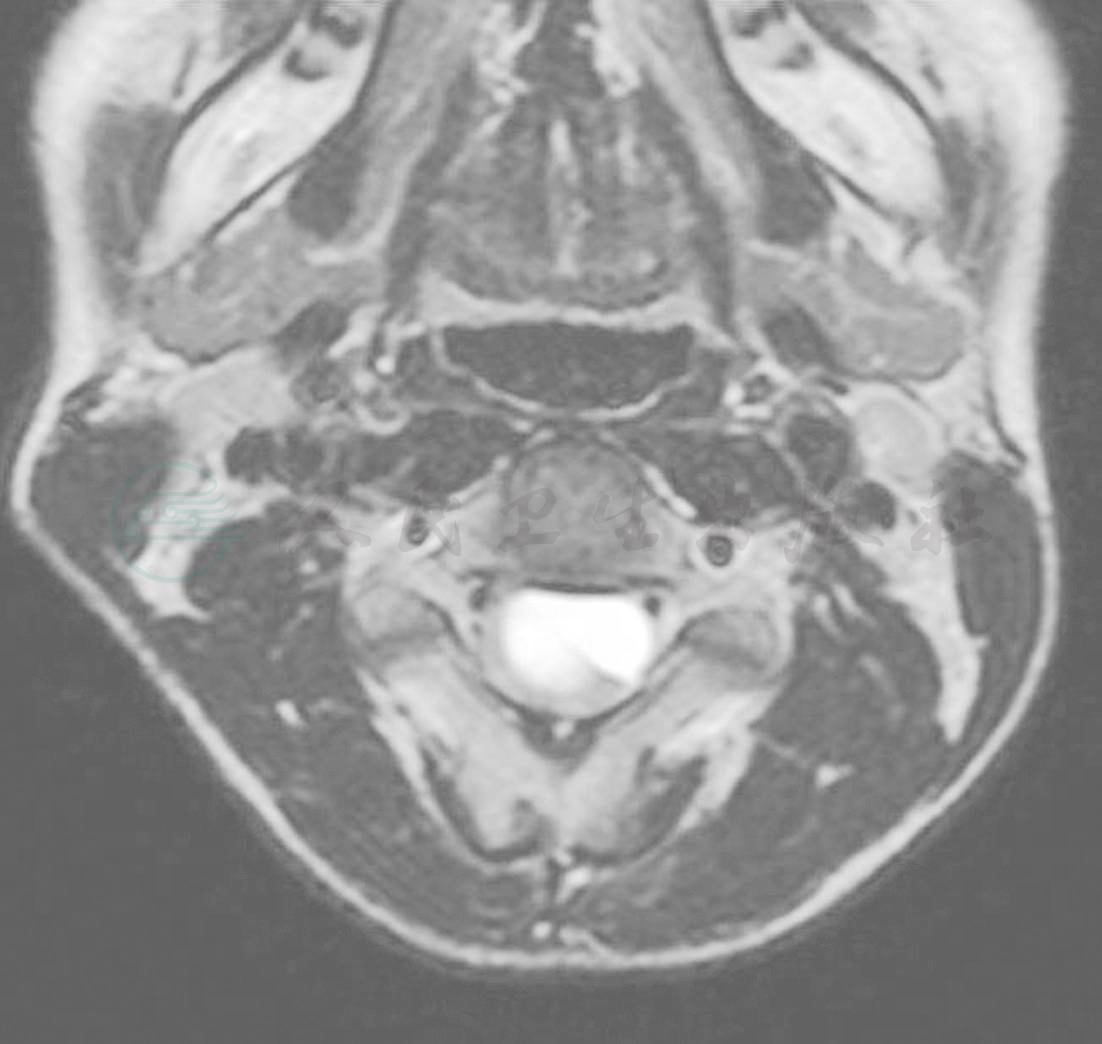

术前磁共振(MRI)示:C3-4段椎管内脊髓前缘见圆形长T1长T2信号影(图1),其边界清晰,内部信号均匀,颈髓受压变形后移,轴位像可见“脊髓嵌入征”(图2)。颈椎生理曲度变直,各椎间隙未见明显狭窄,椎间盘未见突出。增强扫描后,C3-4椎管内病变未见明显强化(图3)。

图2 术前磁共振(MRI)轴位 可见“脊髓嵌入征”

图3 术前磁共振(MRI)增强扫描后,C3-4段椎管内病变未见明显强化